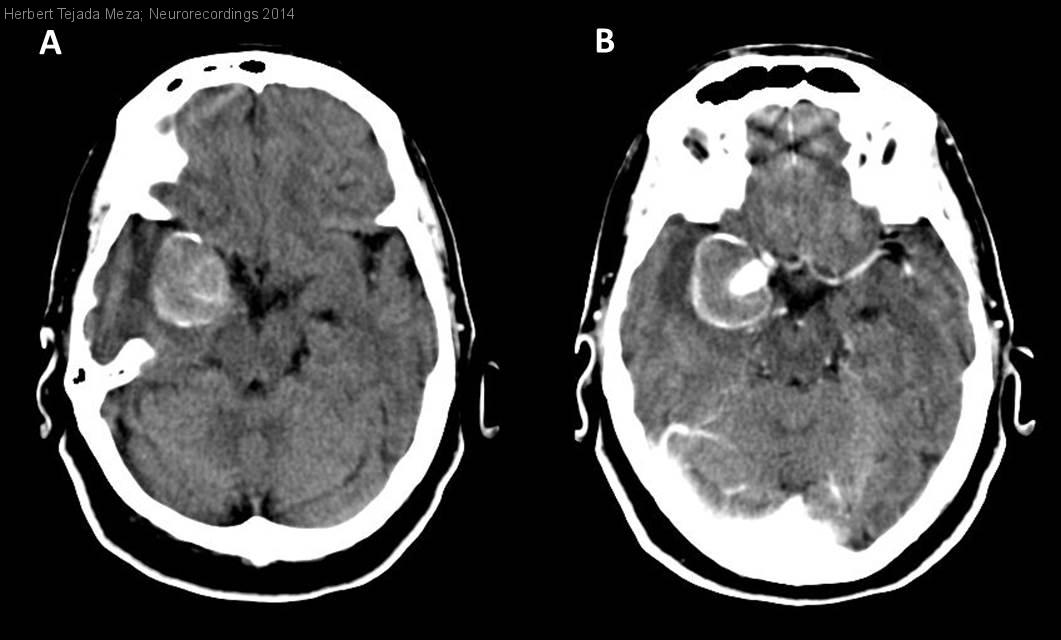

Aneurisma gigante intracraneal asintomático

Mujer | 76 años

Diagnóstico final: Aneurisma gigante intracraneal asintomático

Neurología: Patología cerebrovascular

Etiología: Malformación vascular

Mujer de 76 años hipertensa, sin historia de afectación renal, no fuma ni bebe alcohol, niega sufrir cefaleas u otro antecedente de interés. No tiene familiares que hayan padecido alguna hemorragia intracerebral o subaracnoidea. Consulta...